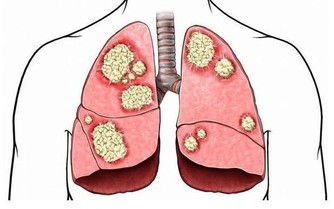

男人的身體健康與自己的前“腺”息息相關,前列腺炎雖然不是什麼大病,但也讓不少男性望而生畏。

男性的排尿時間如果明顯變長,而且有滴滴答答、尿不盡的感覺,或者出現尿無力、排尿困難,中老年男性起夜增加等症狀,都要懷疑是否患上前列腺疾病。